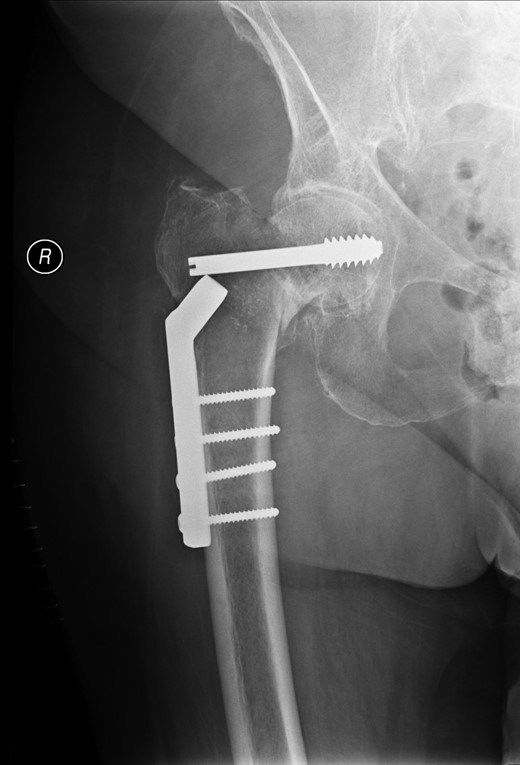

Post-operative nausea delayed immediate attempts at rehabilitation. Although she sat out in a chair, transfers were accomplished with a hoist. At 10 days, post-operatively she was transferred to a peripheral hospital, where rehabilitation commenced with a 2-min period of standing with support. The following morning she complained of greatly increased pain in the operated hip. A radiograph showed that the screw had separated from the barrel, as shown in Fig. 3.

The patient was referred for surgical revision and was treated with a total hip arthroplasty. She made a satisfactory recovery.